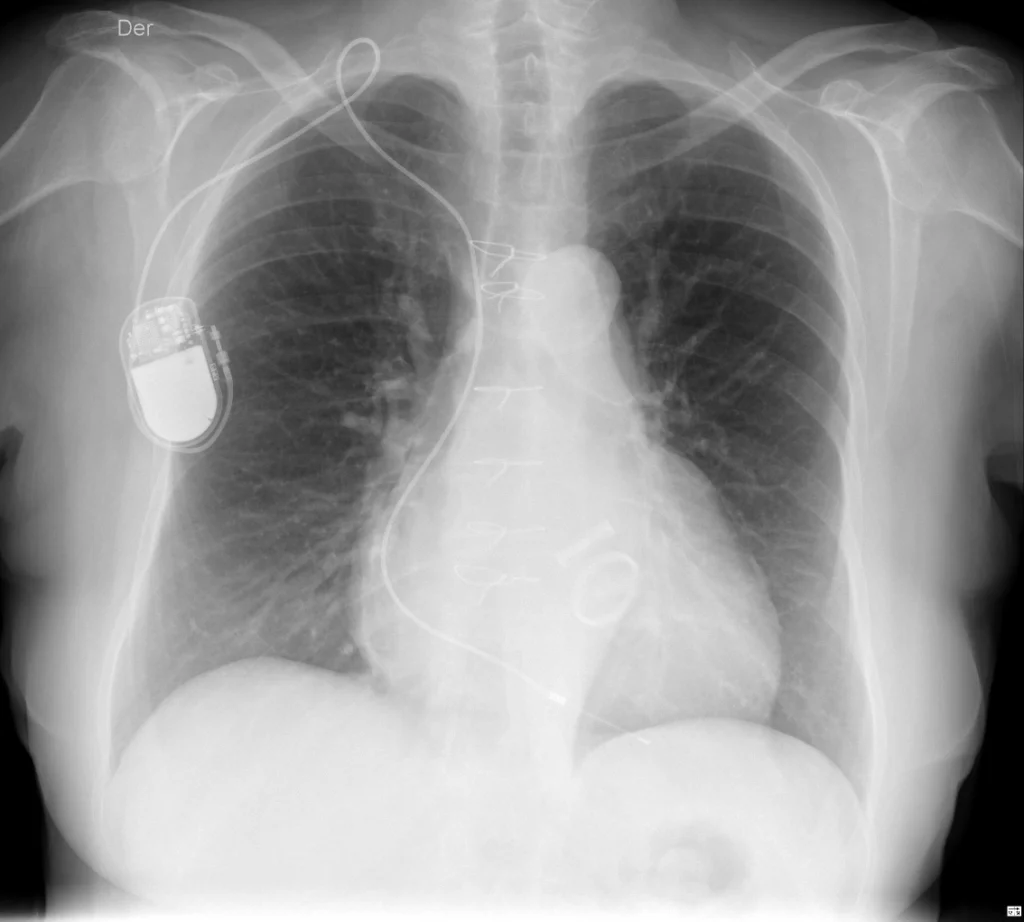

Rx de tórax PA. Sutura esternal, válvulas mecánicas aórtica y mitral y marcapasos cardiaco unicameral con densidad metálica. Se observa además aumento del área cardíaca, signo del tercer arco y aorta elongada.